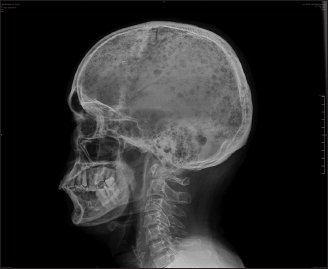

Serum-free kappa light chain was normal, but serum-free lambda was 25.1 mg/dl (elevated) with altered free kappa lambda ratio. Beta-2 macroglobulin was 5.57 which was elevated indicating stage 3 of the disease. In view of right-sided basal crepitations, computed tomography (CT) of the thorax was done, which showed bilateral lower lobe lung parenchymal opacities with pleural effusion and multiple lytic lesions in the spine. As the spleen was just palpable with diffuse tenderness, CT of the abdomen was done which showed thickening with air density pockets in the right psoas and iliacus muscle and splenomegaly and multiple lytic lesions in the vertebral column with pathological fractures [Figure 2], [Figure 3], [Figure 4], [Figure 5]. As this patient also had significant skin manifestations, suspicion toward osteosclerotic myeloma/Crow-Fukase syndrome was made. Hence, the patient was worked up [Figure 6].

| Figure. 3 Computed tomography abdomen showing organomegaly with multiple lytic lesions over the spine